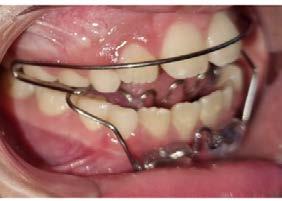

Tratamiento de mordida cruzada anterior

Con aparatología ortopédica funcional en un paciente con dentición mixta. Reporte de caso

La atención a edad temprana durante el crecimiento de los maxilares, puede evitar diversos factores que ocasionan alteraciones en la oclusión. Objetivo: evitar una clase III verdadera bajo tratamiento ortopédico funcional, en un reporte de caso clínico de un niño de 10 años con mordida cruzada anterior profunda. Metodología: tratamiento con aparatología ortopédica funcional, iniciando con encapsulado superior con tornillo de expansión, posteriormente se utilizó un Bimler C, un segundo encapsulado con tornillo de expansión anterior, retomando el tratamiento colocando pistas planas clase III. Resultado:

se logró obtener el avance y la remodelación ósea de la premaxila además del espacio necesario para el OD 23 y eliminación de la mordida cruzada anterior. Conclusión: el tratamiento precoz de las interferencias dentales de la oclusión y un diagnóstico certero de la clase III dental, evita alteraciones en el crecimiento de los maxilares y así se resuelven padecimientos orofaciales agresivos como cirugías ortognáticas.

Metodología

Paciente masculino de 10 años que acude con su madre a consulta y se reporta a su exploración clínica dentición mixta con mordida cruzada anterior con tendencia a clase III. Se solicitó estudio completo, para su

Con los estudios realizados se confirmó clase III dental, depresión del tercio medio en la cara, observándose una discrepancia en el tamaño del maxilar contra la mandíbula y ausencia del OD 63, radiográficamente el OD 23 aún sin erupcionar (Figura 1).

tornillo de expansión ubicado entre el OD 22 y 64. Cementado con ionómero de vidrio en consistencia fluida, el día 12 de enero del 2018, se indicó 2 cuartos de vuelta por semana durante 3 meses, para generar espacio de erupción del OD 23, al retirar el encapsulado quedó a 1mm del borde de los incisivos inferiores con el borde de los incisivos superiores y se obtuvo un espacio de 6 mm en la zona del tornillo (Figura 3).

Figura 4. Bimler C, clase III con arco de Eschler. A) Bimler C, clase III en una vista lateral derecha. B) Bimler C, clase III en una vista lateral izquierda donde se observa un accesorio en U entre el OD 22 y 64. C) OD 11, 12, 21 descruzados.

Se inicia el tratamiento el 8 de diciembre del 2017, con desgaste selectivos en mesial del OD 53 y distal de 73 y 83 para obtener libre movimiento de lateralidad (Figura 2).

Se lleva a cabo la toma de impresiones para la elaboración del aparato ortopédico encapsulado fijo con

4 meses después se continúa con Bimler C, clase III, con accesorio en U entre el OD 22 y 64, colocado en mayo del 2018, con activación del tornillo un cuarto de vuelta por semana y activación del arco de Eschler y resortes frontales en cada consulta mensual. Consiguiendo a los 6 meses descruzar los OD 11,12 y21. Dejó de asistir 5 meses, pero usó su aparato ortopédico sin activar. Regresó en abril del 2019 y se da alta temporal para continuar posteriormente pistas planas clase III, el seguimiento se interrumpió por la pandemia de COVID-19 reanudando atención en diciembre del 2022 (Figura 4).